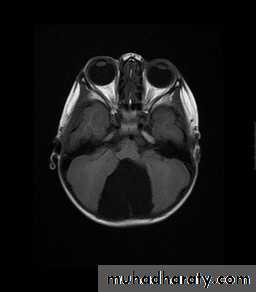

Posterior Fossa Aracnoid cyst

Investigations:

CT Brain

MRI Brain